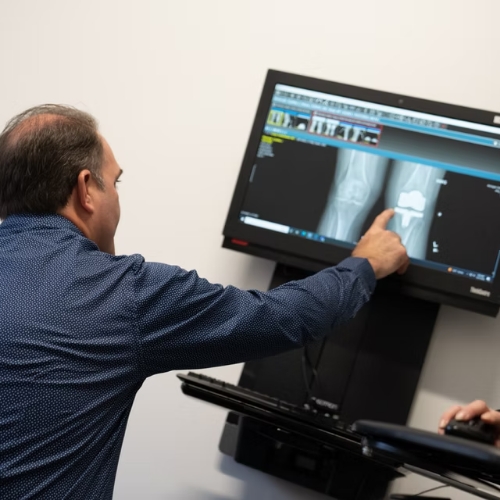

A Step-by-Step Surgical Process

From the moment you meet with a Michigan Orthopedic Center surgeon, you will know your care is in good hands. Our process includes:

Comprehensive Evaluation: